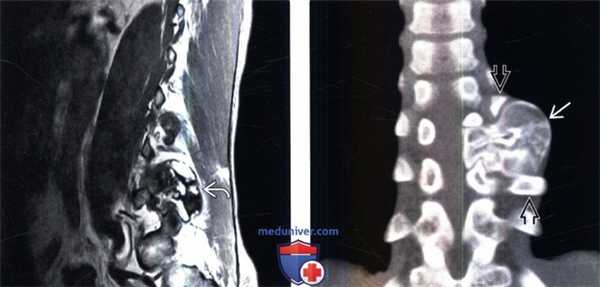

(Слева) Сагиттальный срез, Т1-ВИ: объемное образование вида «цветной капусты», характеризующееся гетерогенной интенсивностью сигнала, исходящее из левого дугоотростчатого сустава L5-S1. Гиперинтенсивность Т1 -сигнала отражает элементы костного мозга.

(Справа) Фронтальный КТ-срез: остеохондрома, исходящая из левых задних элементов грудного позвонка. Кортикальная пластинка и костномозговое пространство образования являются непосредственным продолжением таковых у подлежащей кости. Смежные ребра оттеснены.